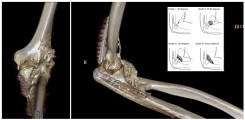

Fig.: 3D-rendered CT of the left elbow in a 25-year-old male with complex trauma to the elbow. Post-traumatically, a massive heterotopic ossification (HO) is formed ventrally and radially in the soft tissues. In the insert, a schematic drawing explaining the classification of HO at the elbow according to Ilahi.